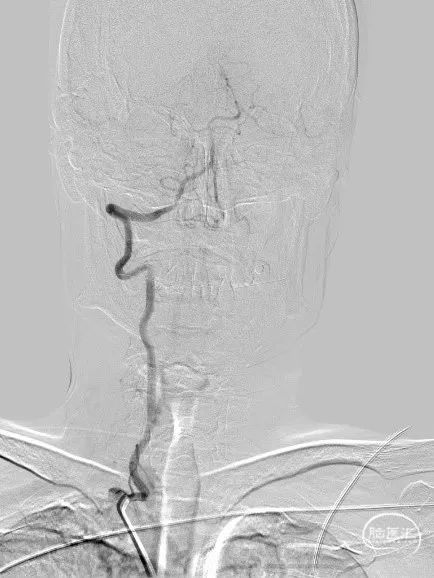

术前影像

脑血管造影DSA:

左侧椎动脉起始部闭塞,残端读片难以分辨,前向血流通过颈外动脉吻合支代偿受限。

右侧椎动脉V4段重度狭窄,并向对侧椎动脉返流。